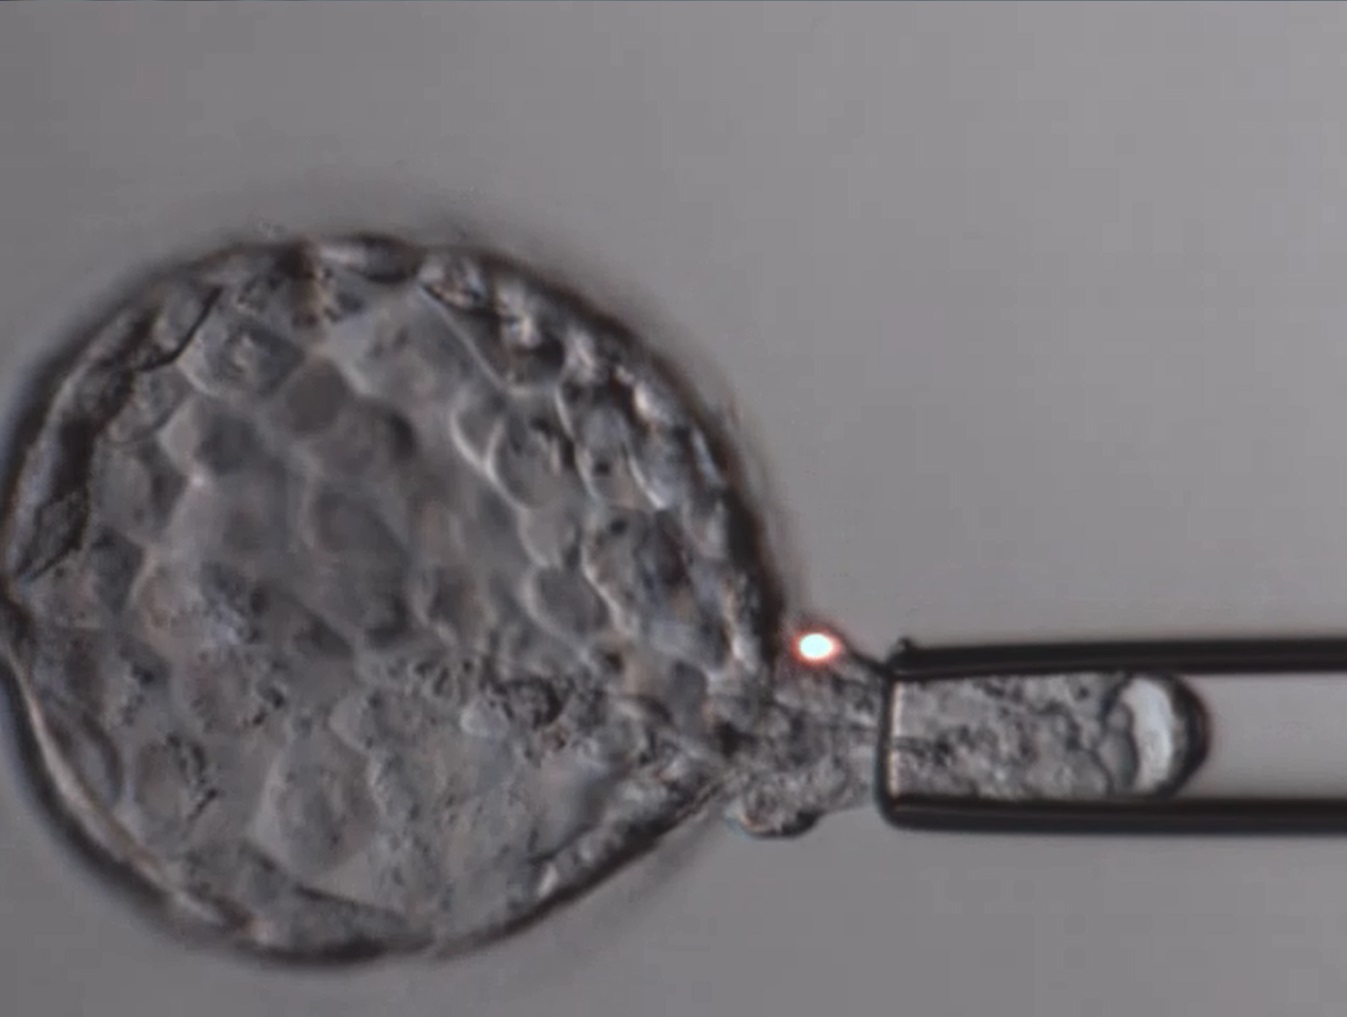

Bei der PID wird aus dem Embryo im Blastocystenstadium am fünften Tag

der Entwicklung, eine kleine Zellprobe aus dem späteren Mutterkuchen,

dem Trophoblast, entnommen. In einem Labor wird genetisch bestimmt,

bei welchen Embryonen die normale Anzahl von 46 Chromosomen vorliegt.

Für diesen Erfolg war eine intensive Vorarbeit im Kinderwunschzentrum

nötig: Bei der sogenannten Trophoblastbiopsie handelt es sich um eine

aufwendige Technik, die ein spezialisiertes Know-How verlangt. Sie

wird mit Miniaturinstrumenten und einem speziellen Laser-Gerät unter

dem Mikroskop durchgeführt. Die Embryologen des Kinderwunschzentrums